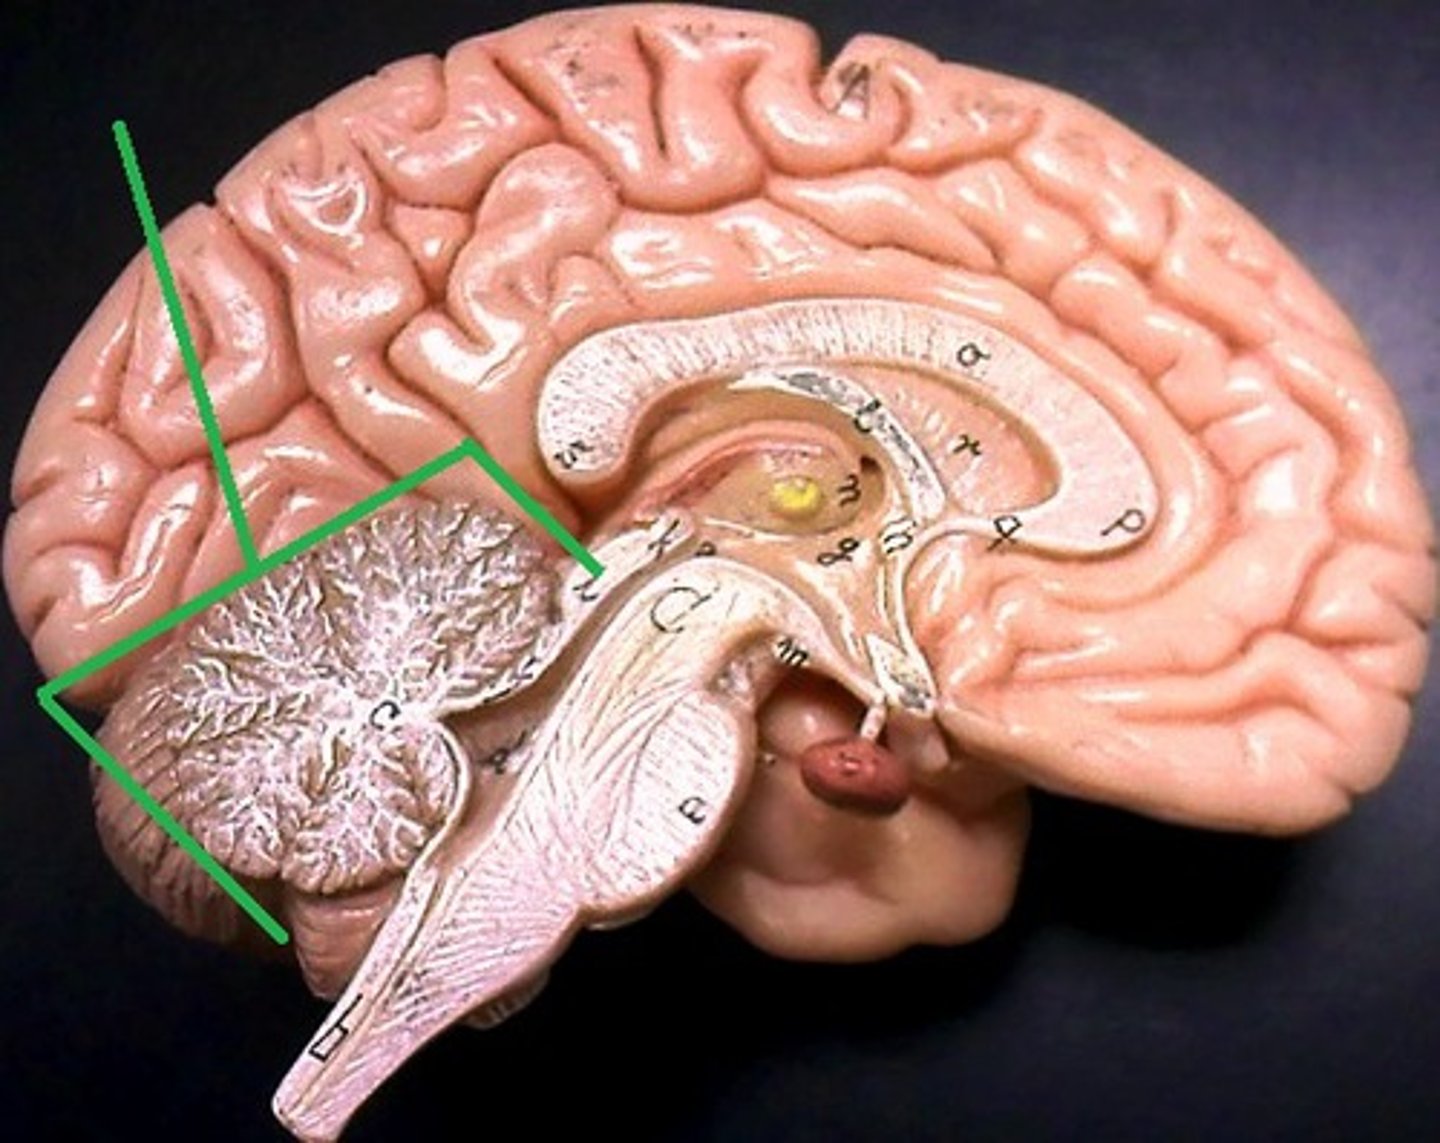

cerebellum

corpus callosum

lateral ventricles

3rd ventricle

4th ventricle

thalamus

hypothalamus

midbrain

pons

medulla oblongata

cerebral aqueduct